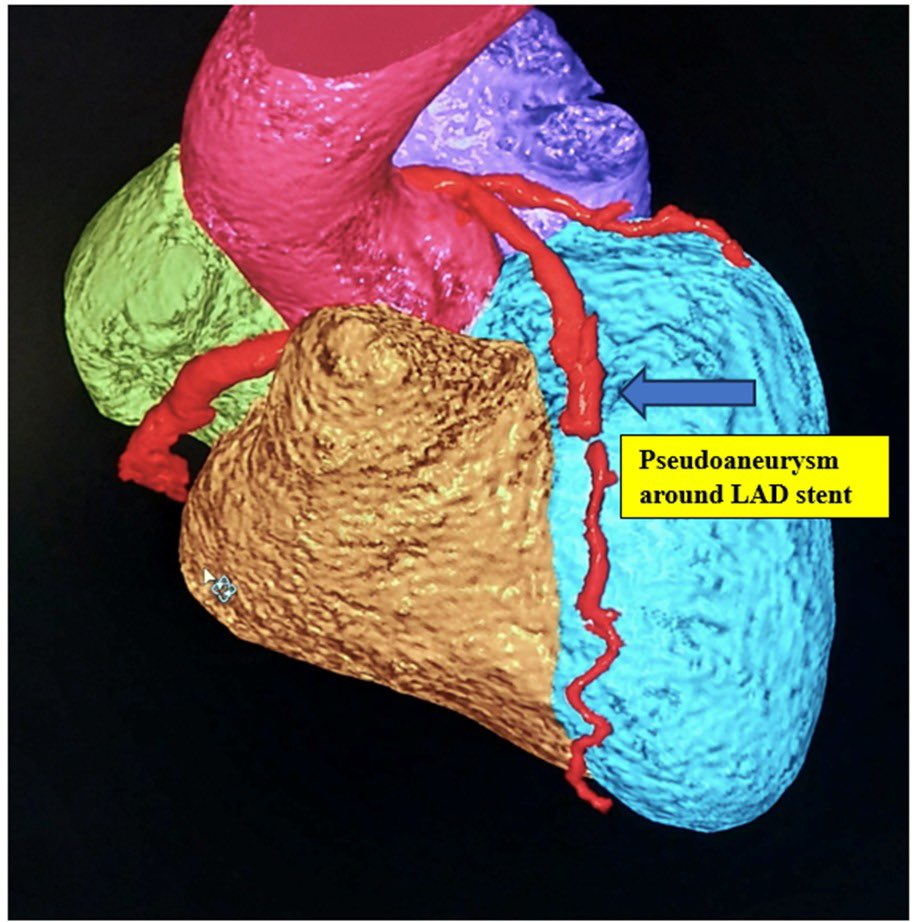

The patients were diagnosed with coronary stent infection and aneurysmal dilatation of the coronary artery following Percutaneous Coronary Intervention (PCI). This condition is a highly complex “iatrogenic” complication, a rare adverse effect resulting from previous medical procedures conducted at various civil and private hospitals across India.

- Extraction and Exclusion: The infected coronary stents and the resulting aneurysms (bulges in the artery wall) were surgically removed or isolated.

- Bypass Grafting: Surgeons performed bypass grafting distal to the affected segments to ensure continued blood flow to the heart muscle.